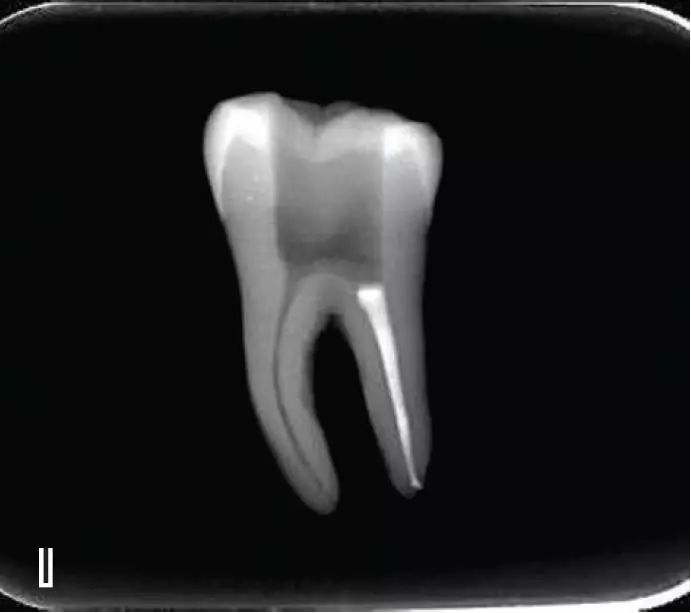

热牙胶根中上段的充填

在完成根尖段的充填后,使用热塑牙胶注射仪对根管中上段进行分层充填,一般分2~3次完成充填,每次充填均使用相应直径大小的垂直加压器进行加压。拍片确认充填效果。